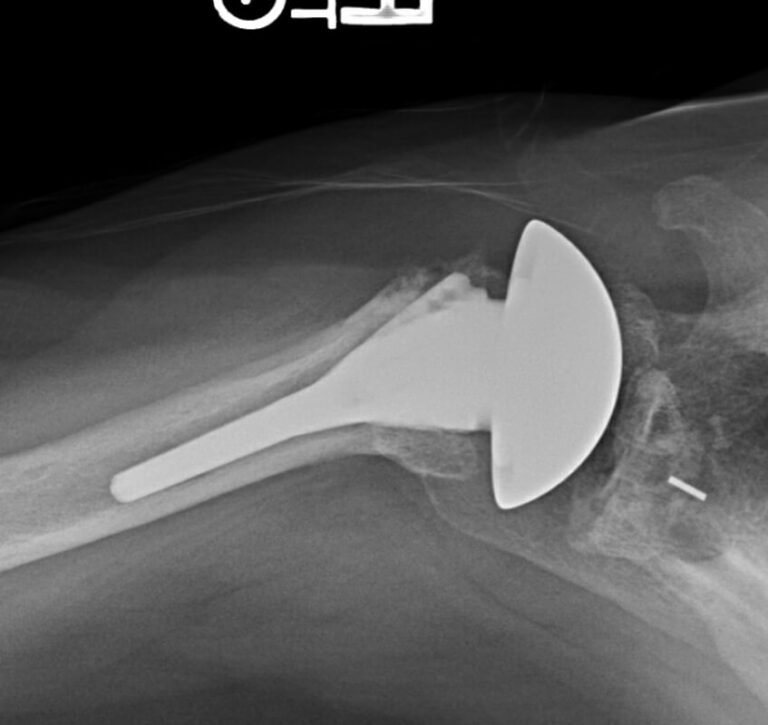

DePuy, Global Unite